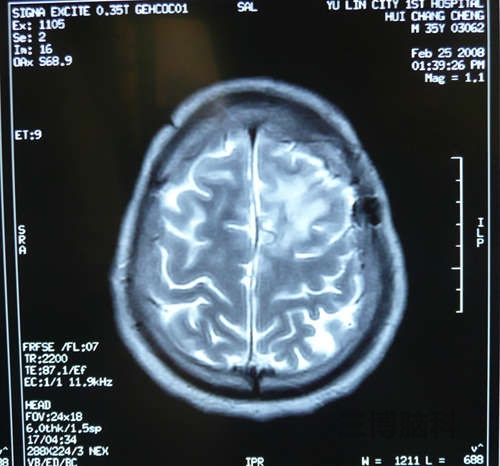

小脑蚓部占位性病变(囊肿)切除术案例

患者赵某某,40岁,男性,北京人,于2014年2月13日以阵发性头晕头痛3月,加重伴呕吐1周入院。 现病史: 患者于3月前2017-06-01

脑囊肿头痛病案

患者某某,男34岁,今年5月份开始头痛,一直很频繁,主要是右侧后部,剧烈疼痛,胀痛,已经严重影响工作和其他2017-06-01